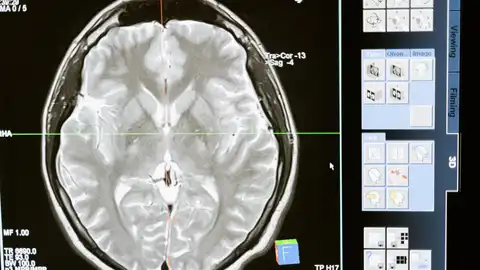

Un chip cerebral que podría leer los movimientos cerebrales para restaurar algunas funciones perdidas por problemas como infartos o esclerosis lateral amiotrófica.

Esto se ha producido tras la aprobación de la Administración de Fármacos y Alimentos (FDA, en inglés) para que Nueralink pudiese hacer estudios con humanos. Debido a esta aprobación, la compañía ha colocado un pequeño implante cosméticamente invisible en la parte del cerebro que planifica los movimientos. El dispositivo llamado 'Telepathy', está diseñado para poder leer la actividad neuronal y por tanto es probable que pueda controlar un ordenador o teléfono móvil simplemente con la intención de moverse. Es decir, la función del implante, según informa la Agencia EFE es "leer" la actividad cerebral para, de esa forma, transmitir órdenes que ayuden a restaurar algunas funciones cerebrales.